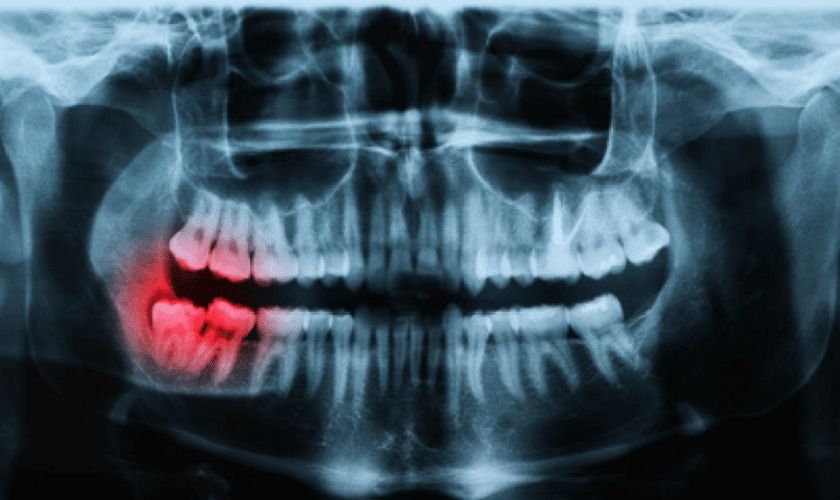

A panoramic dental X-ray, often referred to as a panorex or orthopantomogram, captures the entire mouth in a single image. Unlike traditional dental X-rays that focus on a few teeth at a time, this technique provides a wide-angle view of the upper and lower jaws, teeth alignment, and jawbone structure. This imaging is invaluable for detecting impacted teeth, jaw disorders, bone irregularities, and even early signs of dental decay or cysts.The technology behind panoramic X-rays has improved, making the process quick, painless, and radiation-efficient. Typically, the procedure only takes a few minutes, and the results are instantly available for review. The efficiency of this method contributes to its popularity, but it also raises questions about the cost structure.

Several factors determine the Panoramic Dental X-Ray Cost in Dubai, and it’s not always a simple one-time payment. The price can be influenced by the type of dental imaging equipment used, the location of the dental facility, and the level of expertise required to interpret the images. Advanced digital panoramic machines may result in slightly higher charges due to their superior imaging capabilities and reduced radiation exposure.Additionally, the complexity of the patient’s dental condition may affect the overall pricing. In some cases, dentists may recommend supplementary imaging, such as bitewing or cone-beam CT scans, to get a more detailed view of specific areas. These additional scans could increase the total cost beyond the initial panoramic X-ray.